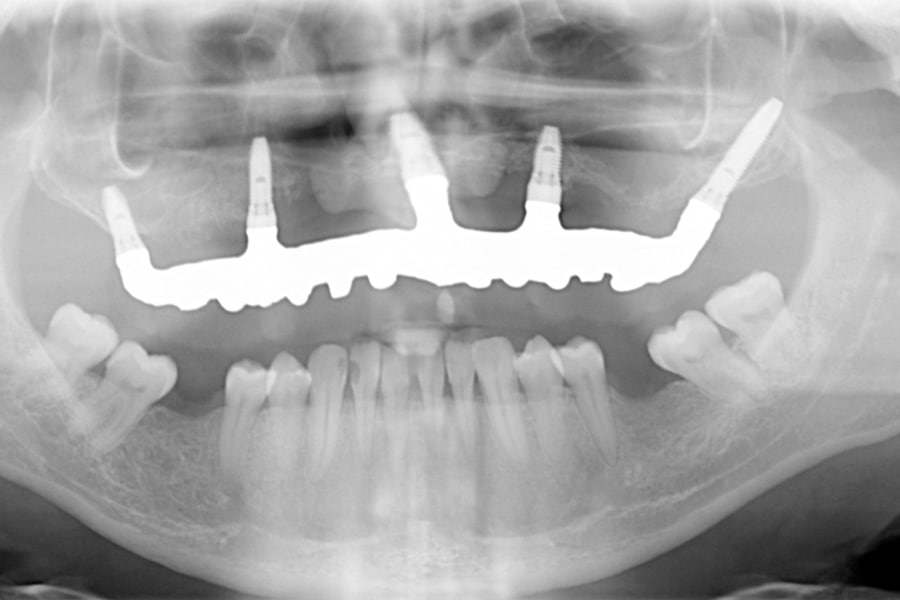

Al paziente, in sedazione cosciente, sono stati posizionati 5 impianti di cui uno nella zona pterigoidea, uno nella zona retro molare e gli altri 3 nella parte ossea anteriore.

La panoramica dopo l’inserimento degli impianti dentali

Il giorno seguente l’intervento al paziente è stata consegnata una riabilitazione provvisoria fissa avvitata sugli impianti secondo il protocollo che viene definito carico immediato.

Il ponte fisso sugli impianti, in accordo con il collega che ci aveva inviato il paziente, è stato progettato in modo da riportare in posizione corretta la mandibola. Già da subito l’aspetto estetico del paziente è migliorato.